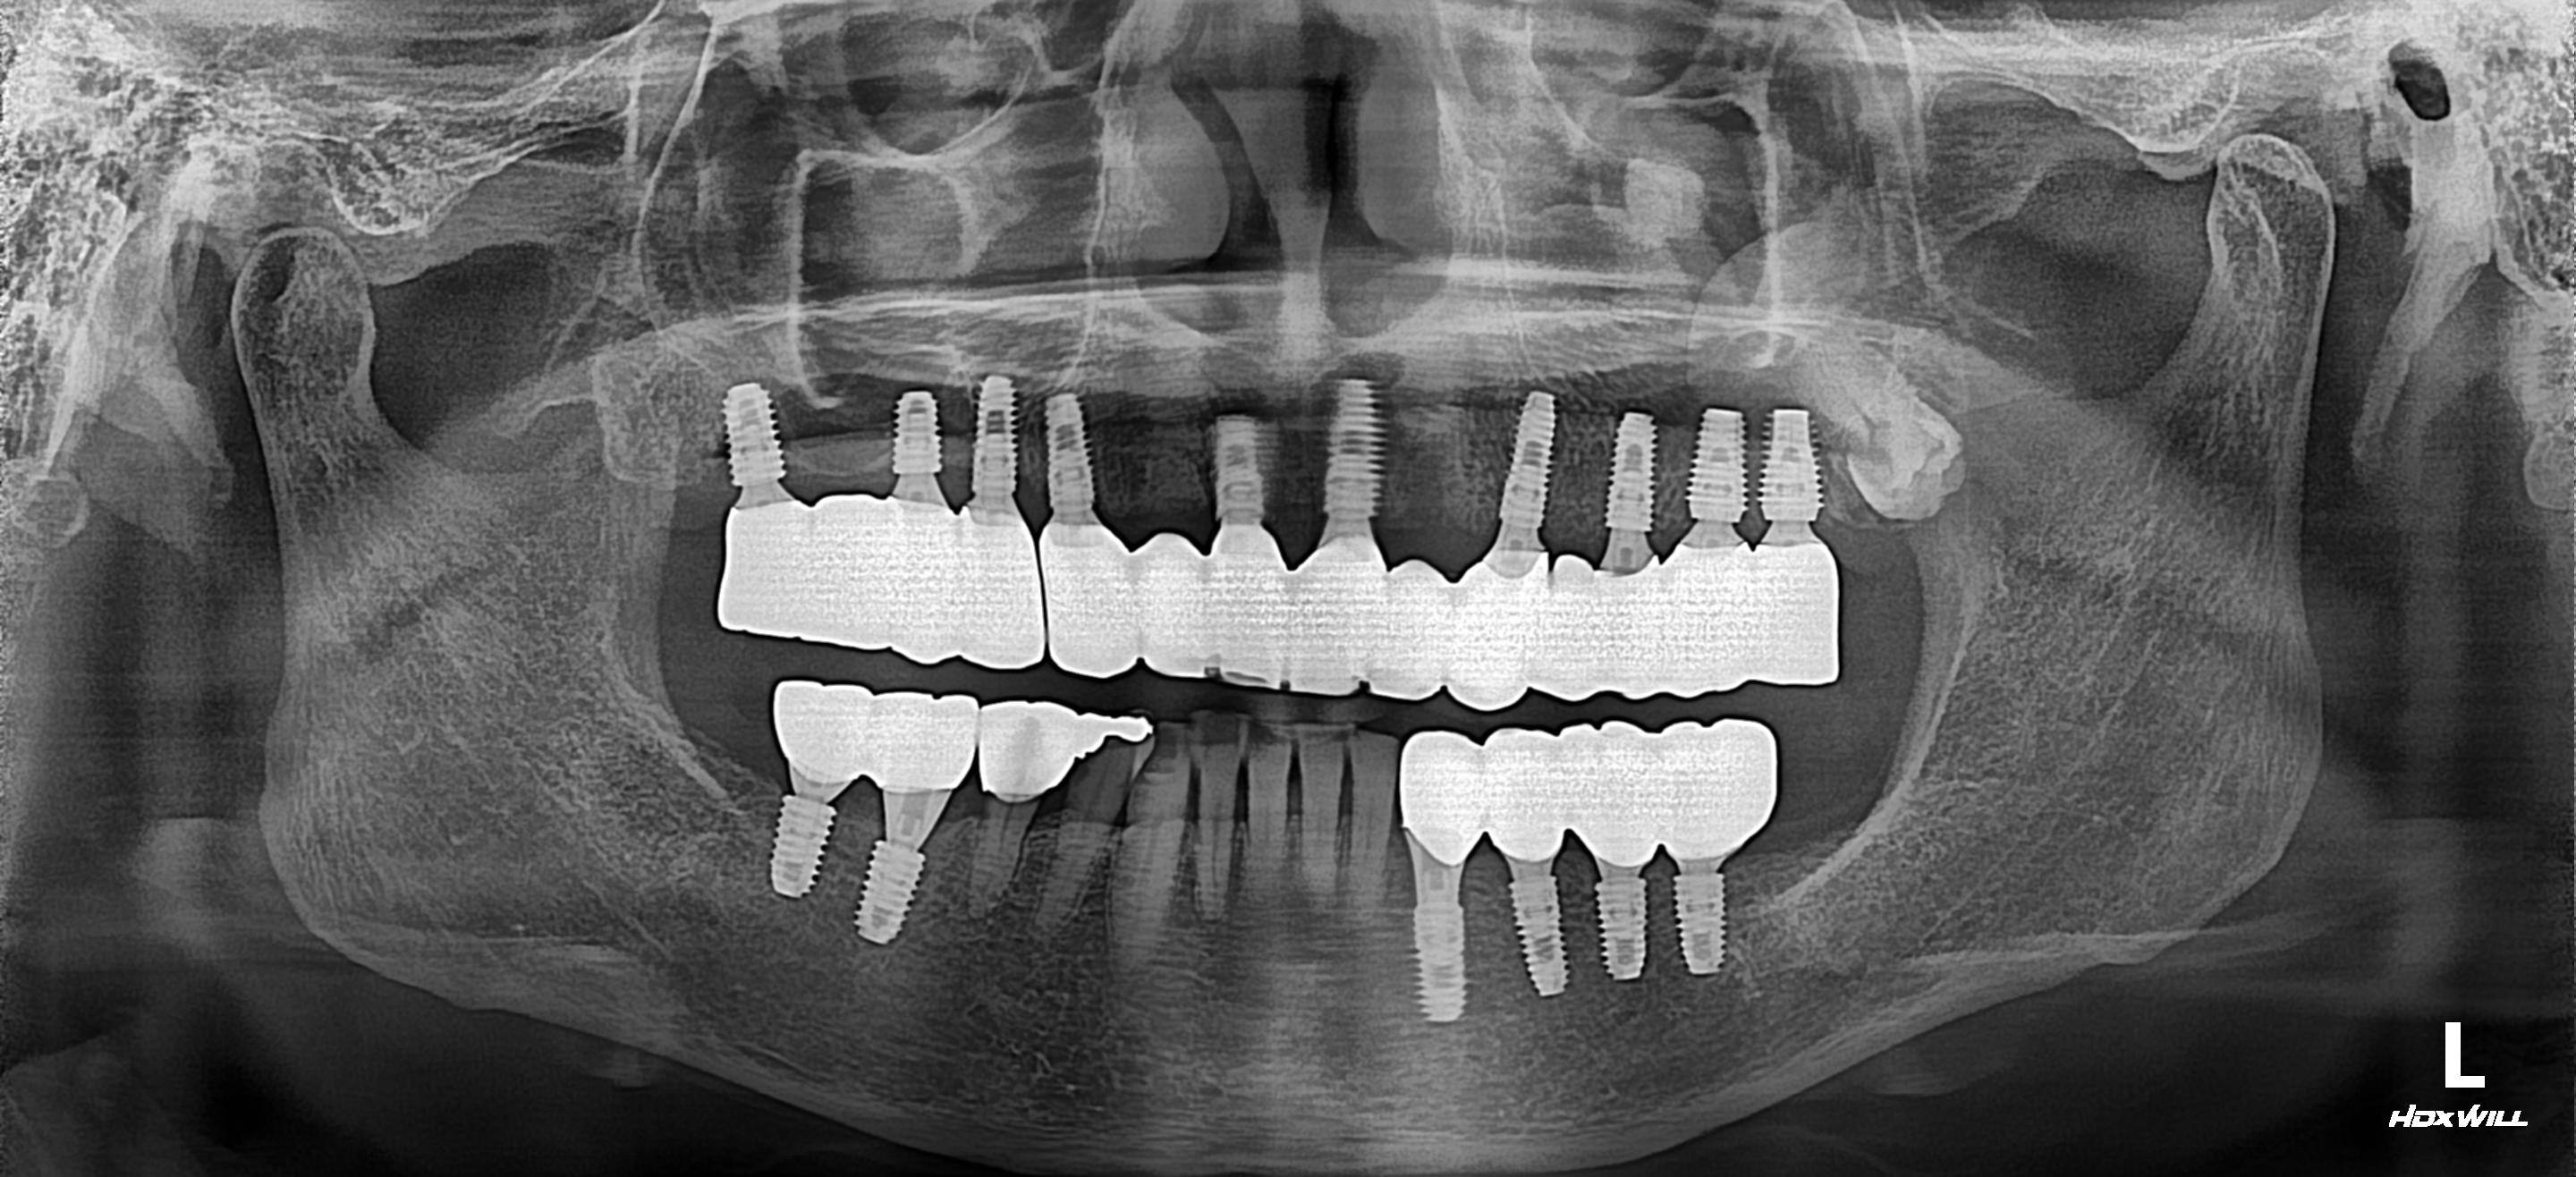

[임플란트] 남은 치아를 모두 뽑고 임플란트 치료를 한 케이스

"이가 다 망가져서 식사를 할수가 없어요. 임플란트 가능하나요?"

이 환자분은 10년전에 치가 몇개 남지 않아 남아있는 치아를 이용해서 브릿지 보철 치료를 하여 사용하다가 내부 치아 우식(충치)과 잇몸 질환으로 치아를 사용할 수 없게 되어 저희 치과에 내원하였습니다.

지방에서 일 때문에 올라오셨는데 5개월정도 서울에 계신다고 하여 남아있는 전체 치아를 발치하고 상.하악 전체 임플란트 치료를 진행하셨습니다.

많은 치조골 이식을 하였지만 치료가 잘 진행되어 기간안에 치료를 완료하여 매우 만족하셨습니다.

이처럼 치아가 기능을 상실하였을 경우 남아있는 치아보다 치조골이 더 중요하기에 적절한 시기에 발치를 진행하여야 임플란트 치료 결과가 좋고 오래오래 건강하게 임플란트를 사용할 수 있습니다.